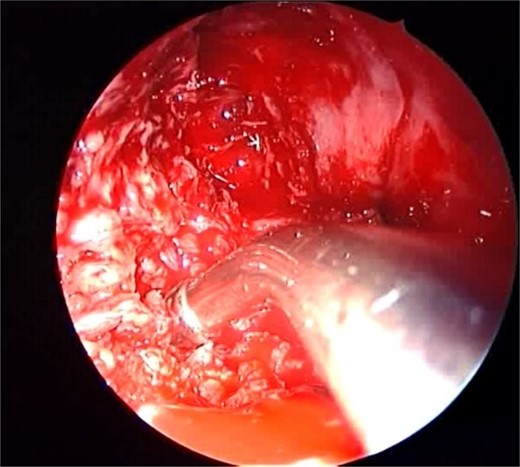

Isolated maxillary acute fulminant invasive fungal sinusitis

A 12-year-old young girl with relapsing acute myeloid leukemia presented with fever, headache, and left maxillary facial pain. Her symptoms were associated with blood-tinged nasal discharge. Nasal endoscopic examination showed friable ulcerative mucosa of the left middle turbinate and osteo-meatal complex which raised a clinical suspicion of invasive fungal sinusitis. Thus, a contrast-enhanced CT scan (CECT) (Fig. 3) was necessary which showed enhancing left maxillary sinus opacity suggestive of acute invasive fungal sinusitis. The patient underwent urgent endoscopic medial maxillectomy with removal of invasive fungal debris (Fig. 4) along with debridement of left middle turbinate, medial maxillary wall, and orbital floor. A diagnosis of invasive mucormycosis was confirmed by histopathology. The patient was started on aggressive treatment in the form of intravenous and oral antifungal medications. She was regularly followed up for the next 5 years with no evidence of recurrence.

Coronal (A) and axial (B) CECT scan images showing left complete maxillary sinus heterogenous opacification.